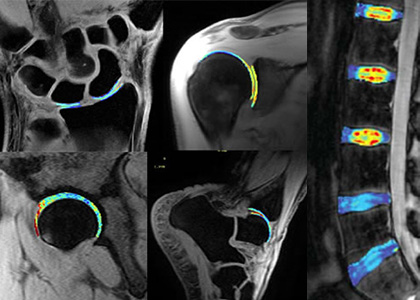

Advanced Musculoskeletal Imaging Angiogenesis Center Cardiovascular Diagnostics & Prevention Computational Life Sciences Consortium for Pain Genitourinary Malignancies Research Genome Center

Musculoskeletal Research Center

Cleveland Clinic's Musculoskeletal Research Center (MSRC) brings together researchers across the spectrum of biomedical discovery—translational scientists and engineers, orthopaedic surgeons, radiologists and imaging scientists, rheumatologists, physiatrists, pathologists, neuroscientists, and biostatisticians—to discover, translate and innovate to improve patient care.

Multidisciplinary investigators in Cleveland Clinic’s Musculoskeletal Research Center study various topics including orthopaedics, rheumatology, spine, physiatry, imaging, pathology, neurosciences and biostatistics.